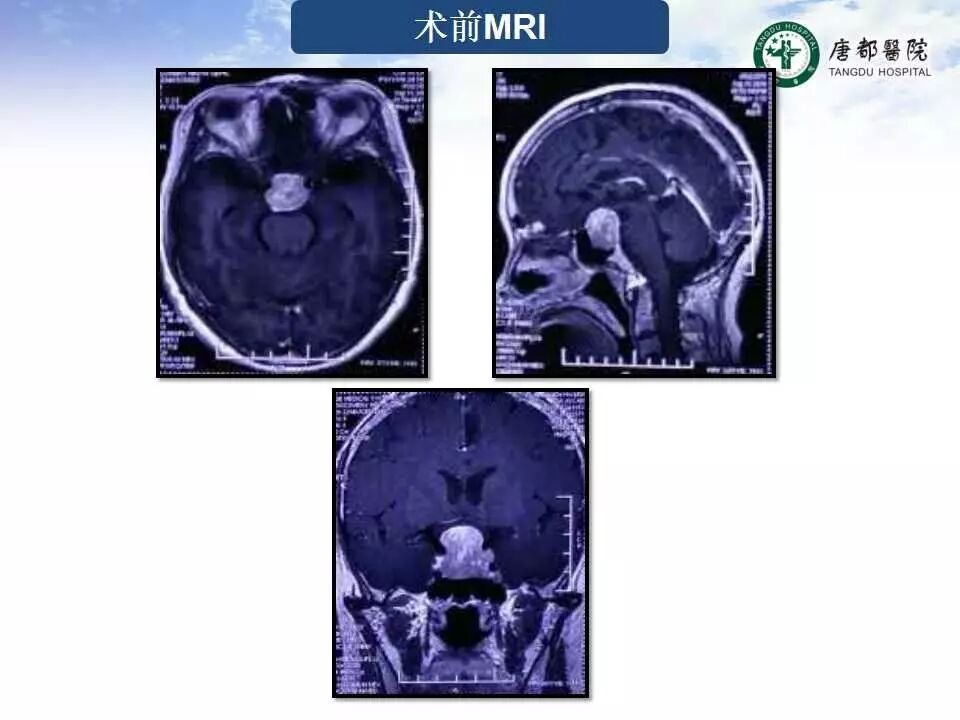

Case 2

长按并识别二维码即可查看该手术视频